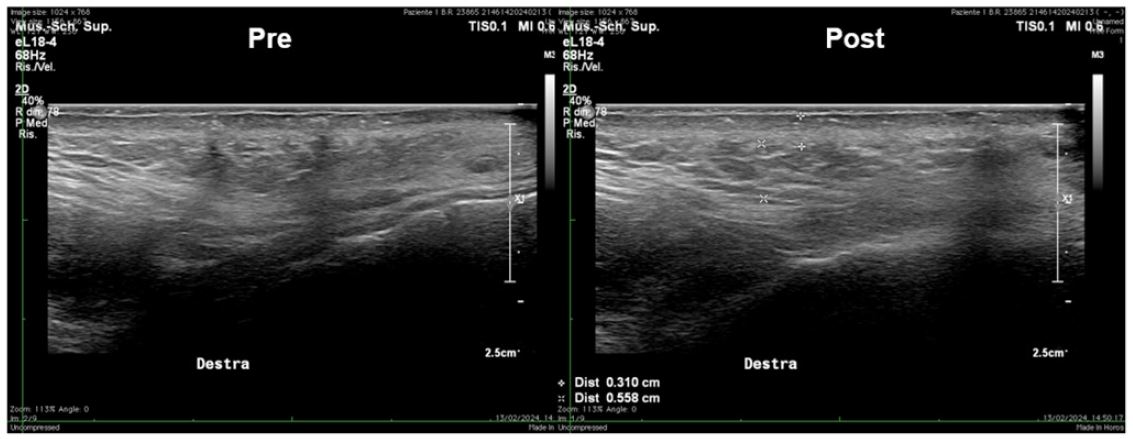

Figure 5: Ultrasound High-frequency (18 MHz) transversal scans at the cheek level, parallel to the mandibular branch before and after treatment, showing reduction in scar extension, decrease of calcifications and an improvement in dermal thickness and trophism.

The morphological examination documented, in the initial ultrasound, a heterogeneous dermis with the presence of some calcifications within its structure and focal areas of relative linear hyperechogenicity, indicative of minor fibrotic scarring (the patient reported having suffered from severe acne during adolescence). However, during the final follow-up, a reduction in scar outcomes was observed, evidenced by a decrease in calcifications and an improvement in dermal thickness and trophism (Figure 5).